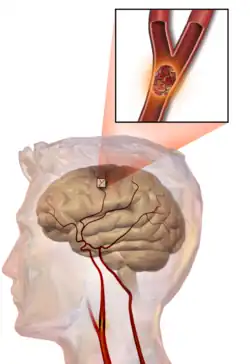

An example of one cause of stroke, due to clogging of an artery. The darkened area on top of the brain are the regions deprived of oxygen.

One of the top causes of death worldwide, strokes are disruptions of the blood supply to the brain. These disruptions can be triggered by a variety of ways, the most common of which are the rupturing of an artery (or hemorrhage), or blockages, which may either by from clots or other obstructions. Whatever the immediate cause, obstruction of the vascular system delivering blood to the brain can quickly lead to the death of cells in the affected areas. Like traumatic brain injury, the exact symptoms and consequences of a stroke depends on the region most affected, however there are some common characteristics. Paralysis or weakness on one side of the body- usually manifested in slurring of speech or drooping of the face- is very common since usually the blocked artery will be responsible for delivering blood to one specific brain hemisphere.